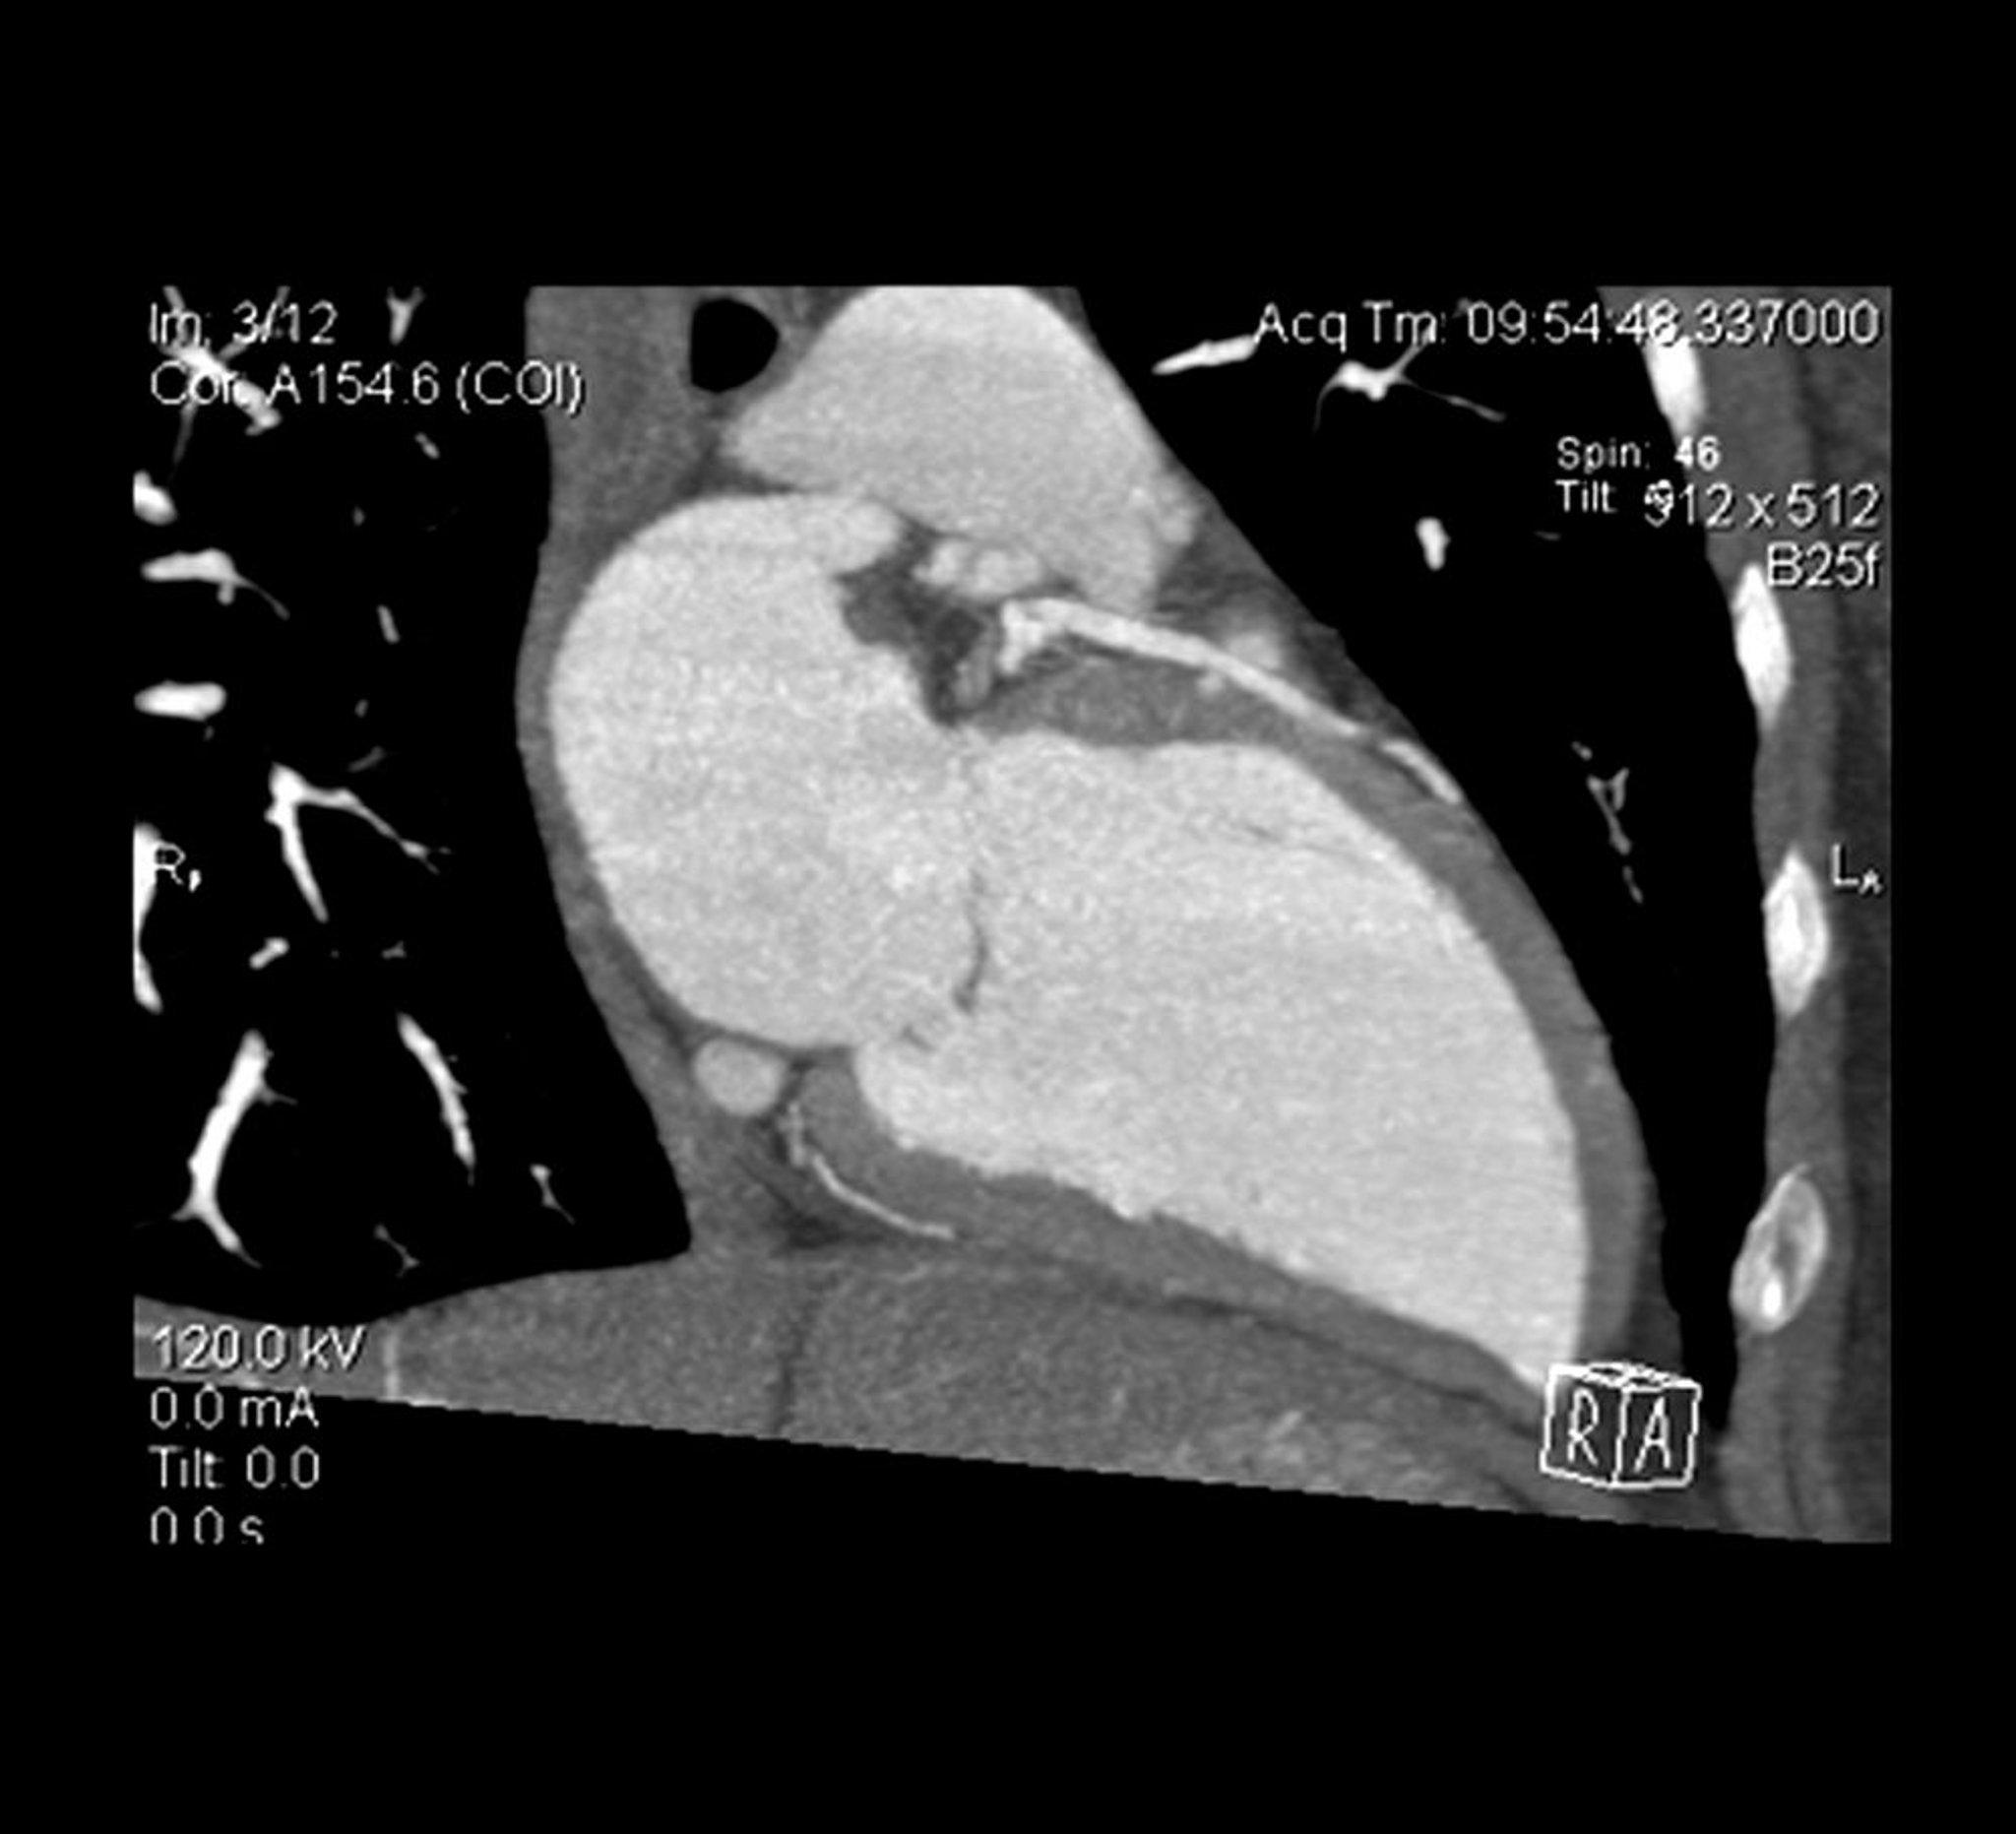

Cardiac CT Angiogram

Cross sectional view of a cardiac CT angiogram shows the left ventricle and the left anterior descending artery.

LIVING ART ENTERPRISES, LLC/SCIENCE PHOTO LIBRARY